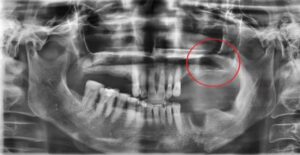

상악동 거상술 환자 실제 사례

부비동은 윗턱 위에 위치한 빈 공간으로, 일부 치아 뿌리가 여기까지 닿습니다. 치아를 발치한 후 남은 뼈가 얇아지면 임플란트를 안정적으로 심기 어려울 수 있습니다.

상악동 거상술로 인해 뼈를 식립하고 뼈의 두께가 (흰색 부분) 한층 두꺼워진 것을 확인할 수 있습니다. 이 후 충분한 검사 후 임플란트를 진행했습니다.